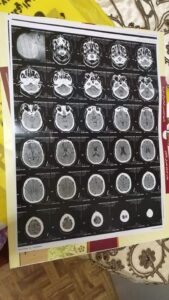

وكشفت شقيقة المصاب أنها عرضت كافة التقارير الطبية والأشعة والفحوصات الطبية على استشاريين في جراحات الرمد والمخ والأعصاب والأنف والأذن، حيث أكدوا أن حالته نادرة ومتأخرة صحياً بسبب توغل الفطر الأسود، وتسببه في تلف الأنسجة بالعين وفكي الفم والعينين، ما قد يتسبب فى وفاته في حال وصول الفطر لخلايا المخ.

وحول حالة المصاب، أوضح وكيل وزارة الصحة أنه تم الإطلاع على كل التقارير الطبية، حيث تبين وجود كسر بالعين اليمنى، وسيتم التنسيق مع مستشفى الرمد الجامعي بجامعة طنطا لاستقبال الحالة وعلاجها، وتوفير الرعاية الصحية الكاملة خلال الفترة المقبلة